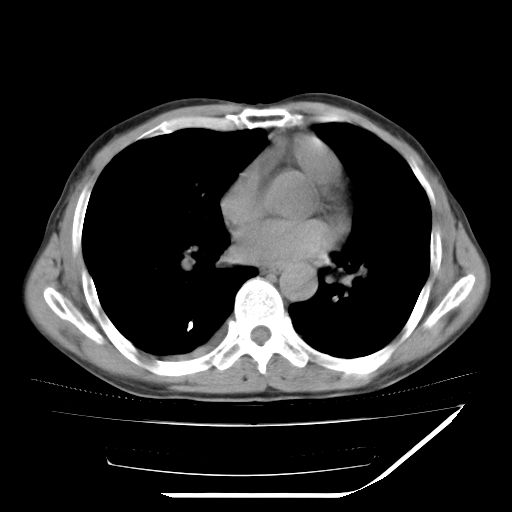

男,59岁,“结核性胸膜炎”30余年,胸部经常疼痛,多次x检查提示“肺部”炎症。腹部疼痛5日,b超提示:“肝内短管结石,余显示不清,建议进一步检查。”

两肺结核并右侧胸腔积液;脾脏、腹腔及腹膜后淋巴结结核[陈旧性];肝内胆管结石

胸部腹部都是结核(双肺。纵隔淋巴结,肝脏,脾脏,肠系膜)

两肺结核并右侧胸腔积液;脾脏、腹腔及腹膜后淋巴结结核[陈旧性];肝内胆管结石。直肠息肉?